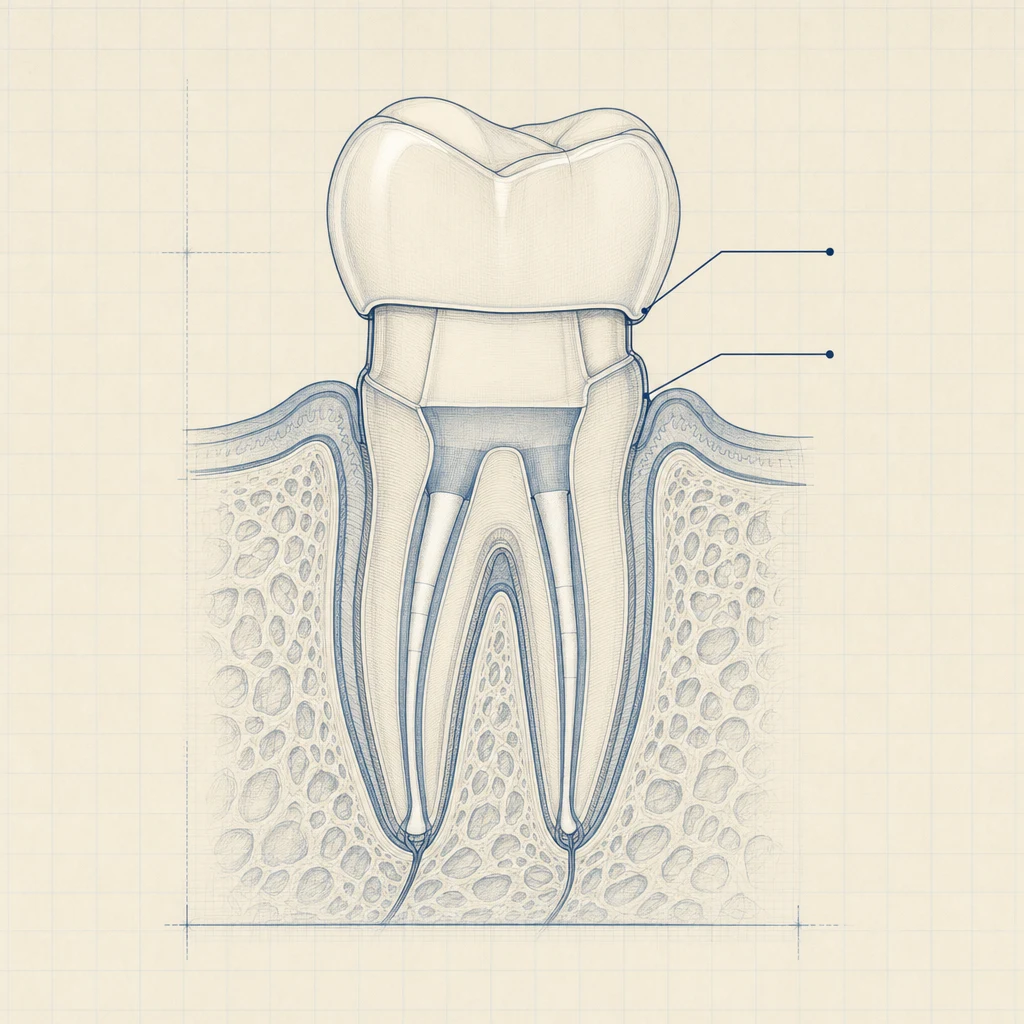

신경치료는 충치·외상·치아 균열 등으로 치아 안쪽 신경(치수)이 감염·염증을 일으켰을 때 진행하는 시술입니다.

- 치아 윗면을 열어 신경관에 접근

- 감염된 신경을 모두 제거

- 신경관 내부를 소독·세척

- 빈 공간을 충전재(거타퍼차)로 채움

- 위에 임시충전 또는 보철

치아를 살리는 마지막 단계의 보존 치료라서, 잘 끝나면 자연치아를 유지할 수 있고, 실패하면 발치로 넘어갑니다.

신경관에 접근하기 위해서는 매우 가는 정밀 기구가 사용됩니다.